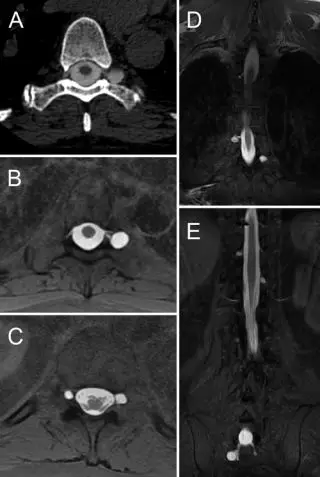

26.多脊髓节段超大型硬膜外血补片治疗自发性颅内低压伴神经认知功能下降1例报道

Multilevel, ultra-large-volume epidural blood patch for the treatment of neurocognitive decline associated with spontaneous intracranial hypotension: case report.

PMID: 28984516 DOI: 10.3171/2017.5.JNS17249

自发性颅内低压(Spontaneous intracranial hypotension, SIH)是一种以直立性头痛、恶心、呕吐和偶发局灶性神经功能障碍为特征的进展性临床综合征。SIH很少伴神经认知功能障碍。硬膜外血补片(epidural blood patch, EBP)常用于SIH的治疗,某些患者可能需要多脊髓节段EBP进行治疗,但保守治疗时这些方法还不够或不起作用。研究通过1例难治性SIH伴神经认知障碍采用多脊髓节段(C3-S3)超大型EBP(120 ml)治疗患者,结果显示术后患者症状消失,预后满意。

【李信晓】